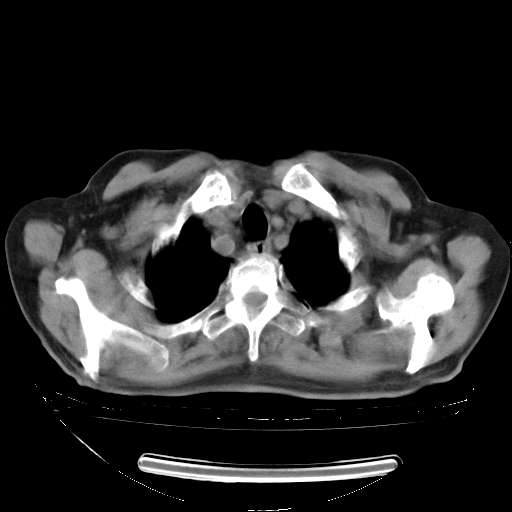

今天复查肺部CT,发现双肺广泛磨玻璃样改变。所以我把3月19日和5月9日相隔50天的肺部CT上传。请大家会诊。

2009年3月19日肺部CT片。

5月9日肺部CT(在4月27日齐鲁医院肺部CT描述部分肺组织磨玻璃样改变,12天后肺组织广泛磨玻璃样改变)

大致读了系列胸部CT:纵隔窗无明显异常,肺窗:从4、27至今:主要是双肺中下野外带可见毛玻璃样改变,目前处于急性肺泡炎阶段,至于原因考虑1、结替组织或胶原血管性疾病所致?2、恶性疾病如恶组在肺部所致的表现或细支气管肺泡癌?3、药物或其它原因如肺蛋白沉着症所致肺泡炎目前不太可能?总之,明天就去请我院的呼吸科、感染科、血液科和临免专家会诊哈。